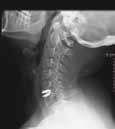

Capitaneada por el Dr. Ricardo Arregui, este equipo está compuesto por 3 neu-rocirujanos, 1 traumatólogo y 1 neurólogo, que atienden una media de 5.314 consultas y realizan una media de 307 intervenciones anuales, dando tratamiento integral a cualquier lesión producida en la columna vertebral y el sistema nervioso: traumatismos craneoencefálicos, traumas raquimedulares, hernias de disco...

El disco dañado se sustituye por una prótesis móvil, que permite la movilidad del cuello.